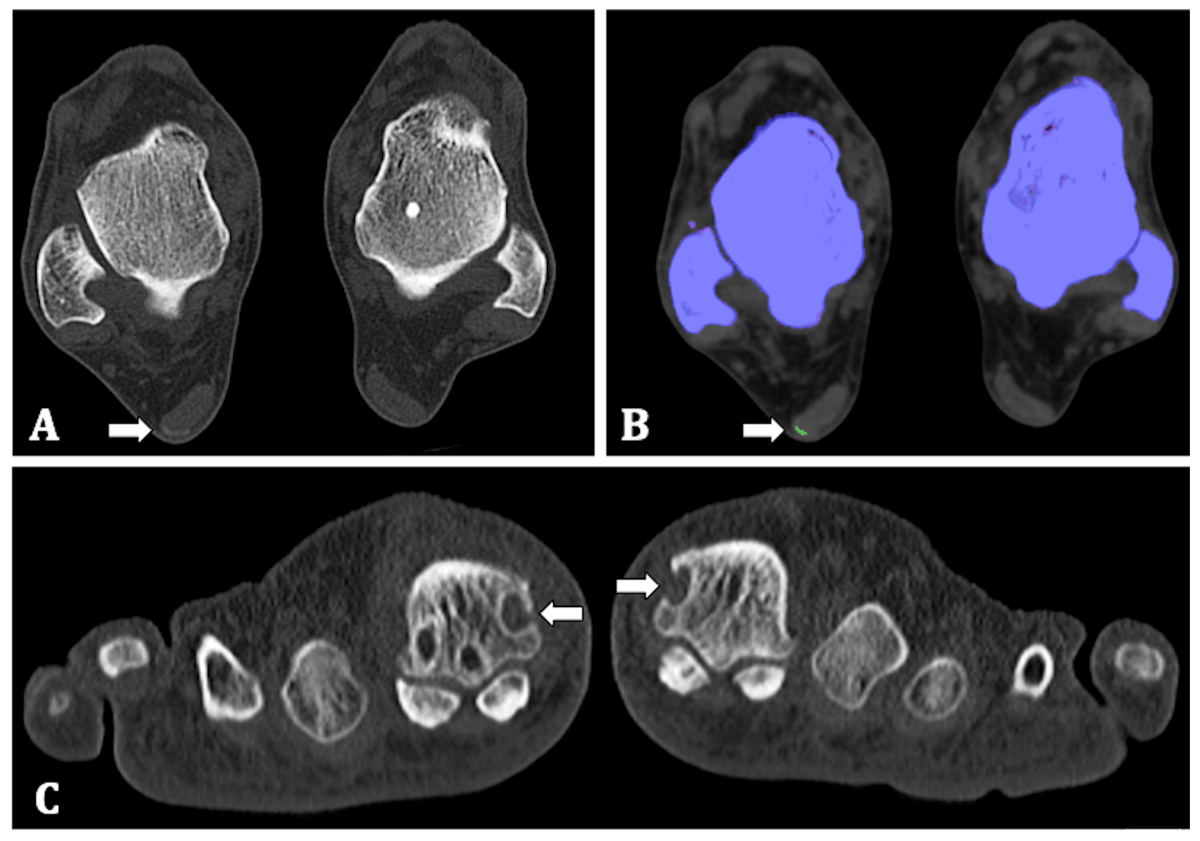

The native CT images showed erosions with a sclerotic border and overhanging edges in the MTP-I of both feet and a higher-density zone in the lateral margin of the Achilles tendon of his right foot with MSU crystal deposition on DECT, all typical features seen in gout [5] (Figure 1).

Figure 1

65-year-old man. (A) Transverse native CT image of both feet at the level of the talus. A higher-density zone is shown in the lateral margin of the Achilles tendon (arrow). (B) Colour-coded images identified the presence of MSU crystals as a green zone (arrow). (C) Coronal native CT image, showing erosions with sclerotic border and overhanging edges in the head of the first metatarsal bone both left and right (arrows).